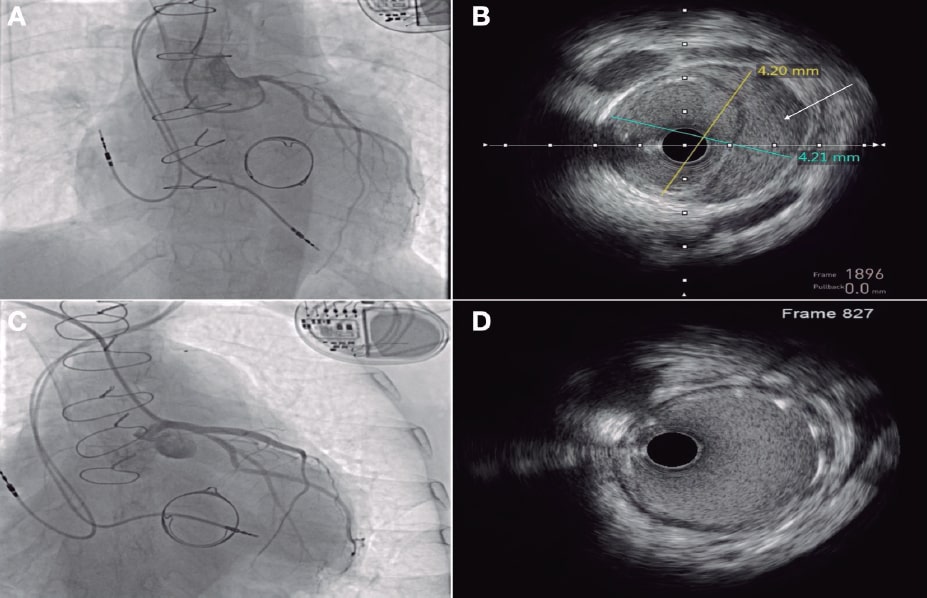

Mujer de 55 años con canal auriculoventricular incompleto con reparación del cleft mitral y cierre con parche del defecto tipo ostium primum y posterior implante de bioprótesis mitral (Carpentier PERIMOUNT 27, Edwards, EE.UU.) en la edad adulta. Evolucionó con episodios de aleteo auricular izquierdo y se decidió realizar una ablación retroaórtica del nódulo auriculoventricular, por imposibilidad de punción transeptal, con disección yatrogénica del tronco común izquierdo resuelta tras el implante de un stent farmacoactivo (figura 1A-D, vídeos 1 y 2 del material adicional). A lo largo del seguimiento presentó datos de degeneración protésica progresiva (figura 2A-B, vídeos 3 y 4 del material adicional), por lo que se decidió llevar a cabo un implante percutáneo de prótesis mitral valve-in-valve. Se procedió con punción transeptal del parche gravemente calcificado (figura 2C-D) con sistema Versacross (Boston Scientific, EE.UU.) y mediante un catéter deflectable se avanzó una guía de alto soporte que fue capturada en el ventrículo izquierdo, estableciendo un circuito venoarterial. Se realizó septostomía con catéter balón Atlas Gold 16 × 45 mm (BD, EE.UU.), y con gran dificultad, dada la complejidad anatómica, se avanzó una vaina de 26 Fr DRYSEAL (Gore, EE.UU.) hasta la aurícula izquierda, a través de la cual se implantó una bioprótesis SAPIEN 3 Ultra 26 (Edwards, EE.UU.) con inflado nominal + 2 cm3. Se observó una buena expansión, con ligera protrusión en el ventrículo izquierdo sin conflicto con el tracto de salida (figura 3A-D, vídeo 5 del material adicional). Se dio el alta hospitalaria a la paciente con una función protésica normal que se mantenía al año de seguimiento (vídeo 6 del material adicional). La paciente firmó el consentimiento informado.

Figura 2.